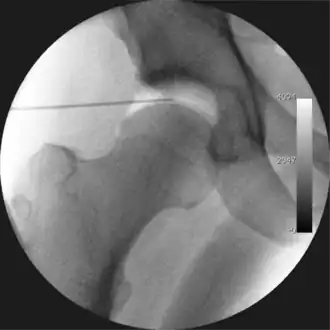

Figure 3. Fluoroscopic picture showing a mild amount of distraction of the hip before insertion of any instruments

The procedure is performed with the patient asleep (general anaesthetic) or under spinal anaesthesia. There are two widely used methods, one with the patient on their back (supine) and the other on their side (lateral decubitus). Which is used is down to the surgeon's preference. To gain access to the central compartment of the hip joint (between the ball and socket), traction is applied to the affected leg after placing the foot into a special boot. (See fig. 2) There is specifically designed equipment for this, although some surgeons use a 'traction table', initially designed to help in the operative fixation of broken thigh and lower leg bones. The amount of traction (or pull) needed is assessed with the help of fluoroscopy (low-dose portable x-ray). (See fig. 3) It is usually not possible to distract the ball from the socket with traction alone by more than a few millimetres. Once the surgeon is happy that they will be able to gain access to the hip joint (i.e. the ball will distract from the socket by a small amount), the patient is then painted with antiseptic and the surgical drapes applied.